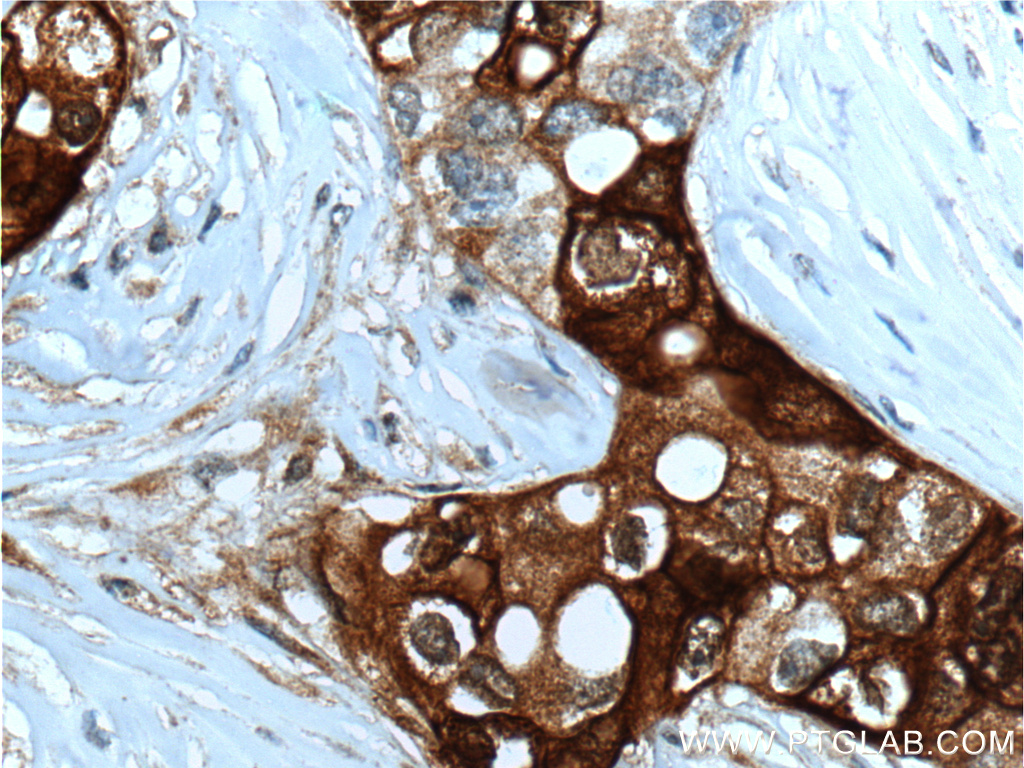

| Positive IHC detected in | human breast cancer tissue Note: suggested antigen retrieval with TE buffer pH 9.0; (*) Alternatively, antigen retrieval may be performed with citrate buffer pH 6.0 |

Mammaglobin A, also known as SCGB2A2, is a member of the secretoglobin superfamily. Mammaglobin A is a breast cancer-associated antigen almost exclusively over-expressed in primary and metastatic human breast cancers, making it a specific molecular marker and a potential therapeutic target for breast cancer. This monoclonal antibody is raised against full-length of 93-amino acid human mammaglobin A.